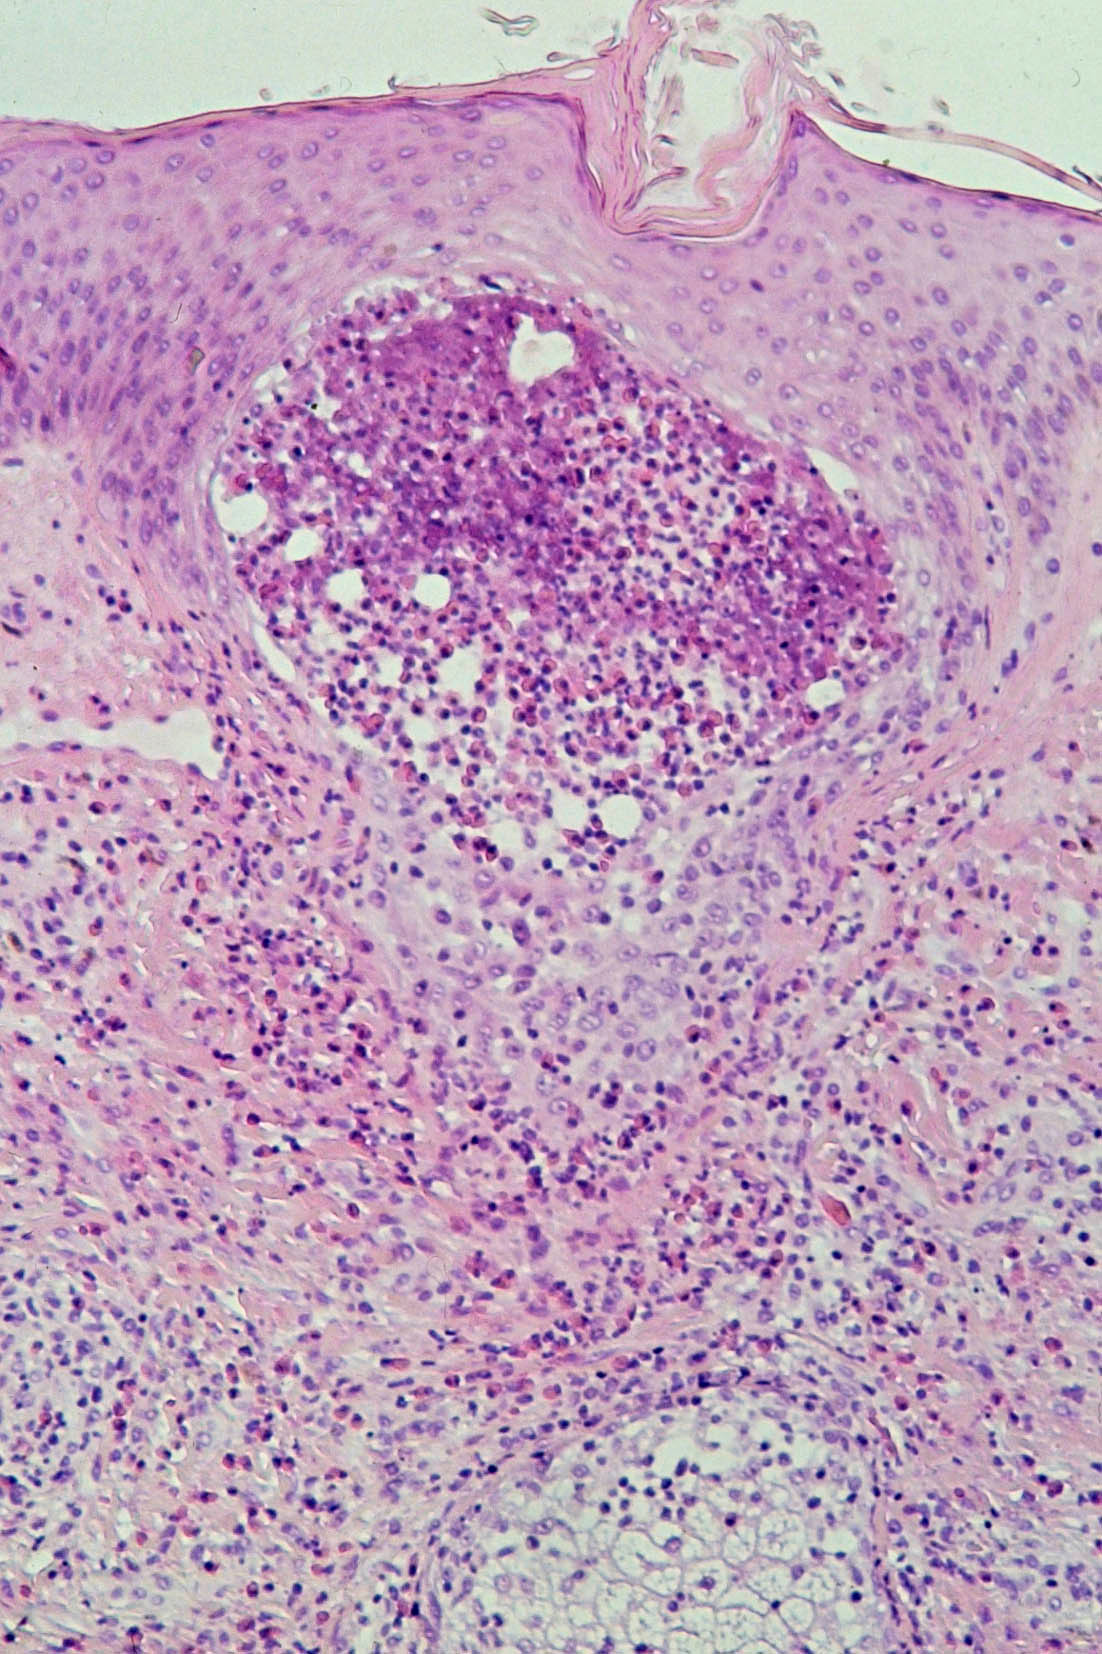

![Eosinofiele folliculitis (click on photo to enlarge) [source: www.huidziekten.nl] Eosinofiele folliculitis](../../../images/eosinofielefolliculitis3z.jpg) |

![Eosinofiele folliculitis (click on photo to enlarge) [source: www.huidziekten.nl] Eosinofiele folliculitis](../../../images/eosinofielefolliculitis4z.jpg) |

| eosinofiele

folliculitis |

eosinofiele

PA:Uitgebreid eosinofiel infiltraat, in de follikel en perifolliculair. In het klassieke geval zijn de haarfollikels ter hoogte van de inmonding v.d. talgklier (die soms ook volledig is aangetast) geïnfiltreerd met vele eosinofielen, en enkele mononucleairen en neutrofielen. Tevens bestaat spongiose en destructie van het bovenste deel van de haarfollikel (infundibulum). Ook in epidermis zonder follikels is infiltratie van eo's, met spongiose en intra-epidermale eosinofiele abcesjes. In de dermis is een perivasculair, voornamelijk eosinofiel infiltraat aanwezig.